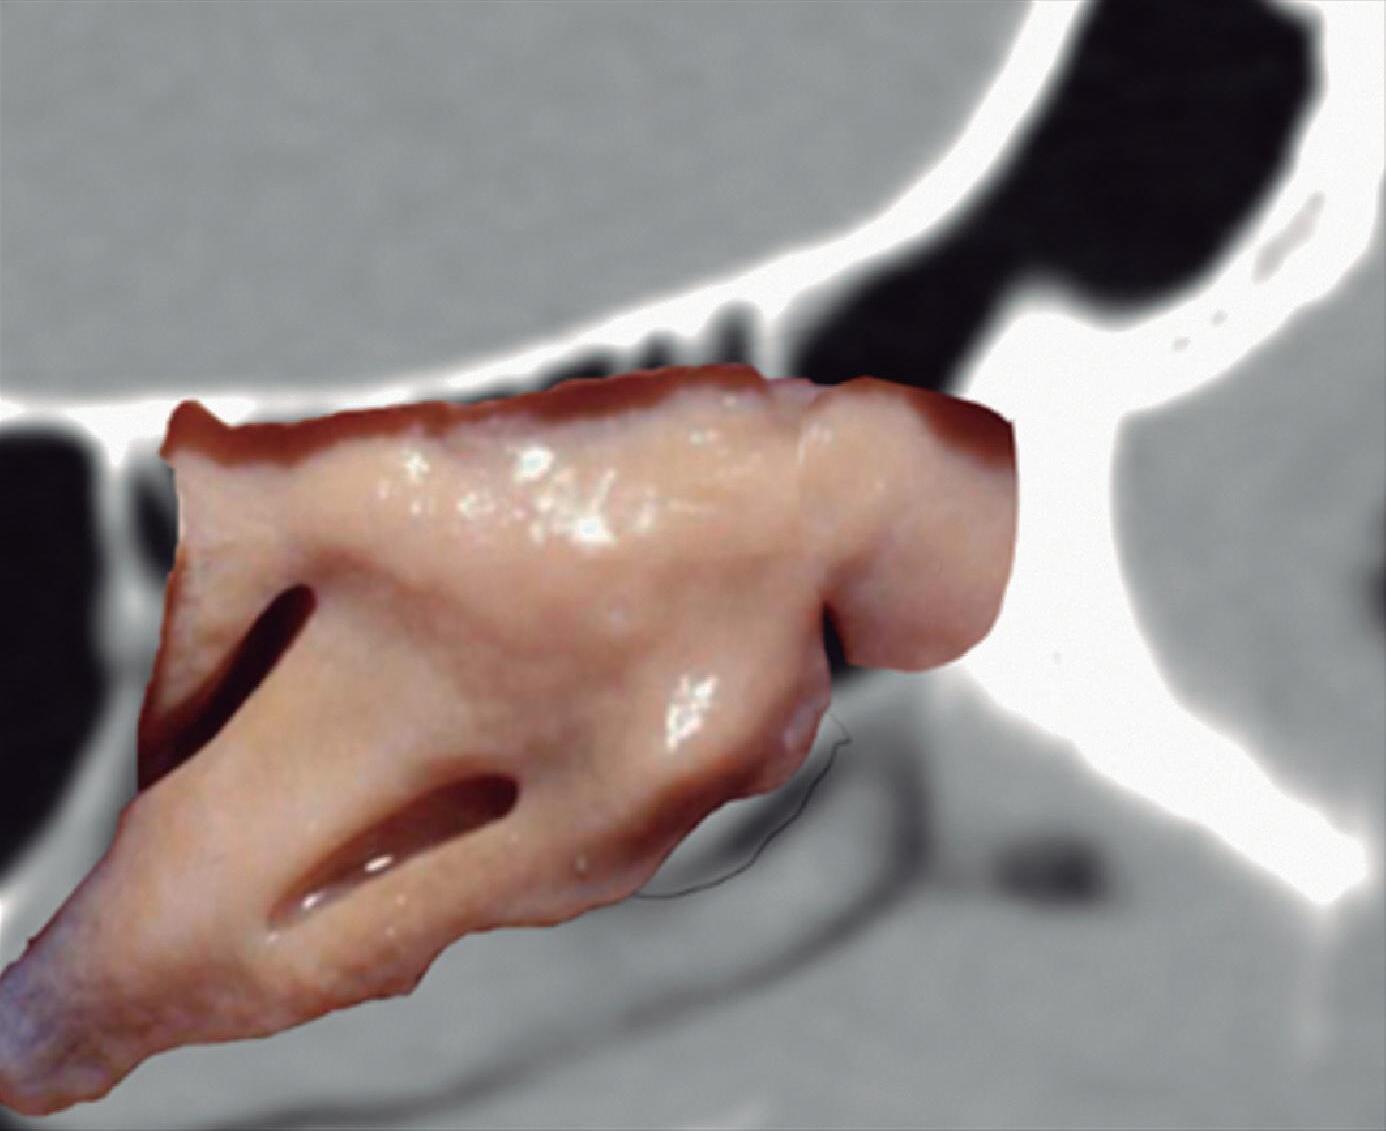

Utilizamos muitas vezes o programa “Nasal Vista”, desenvolvido na Espanha por meu ex-fellow Guillermo San Juan e pelo autor, programa este construído após digitalização de 600 tomografias computadorizadas e que oferece imagens anatômicas detalhadas juntamente com o estudo radiológico, tornando-se uma ferramenta didática muito útil.

1-4. TC e reconstrução 3D com destaque para estrutura etmoidal (em vermelho), funcionando como câmaras de baixa pressão para drenagem do seio maxilar.

1-7. TC com reconstrução 3D mostrando em vermelho apenas o seio etmoidal e não o osso etmoidal, e sua relação com a fossa nasal, o seio maxilar, órbita e fossa anterior.

1-8. Osso etmoidal e seio etmoidal (amarelo) observar o aspecto incompleto do teto do seio etmoidal que será coberto pelo osso frontal (rosa).